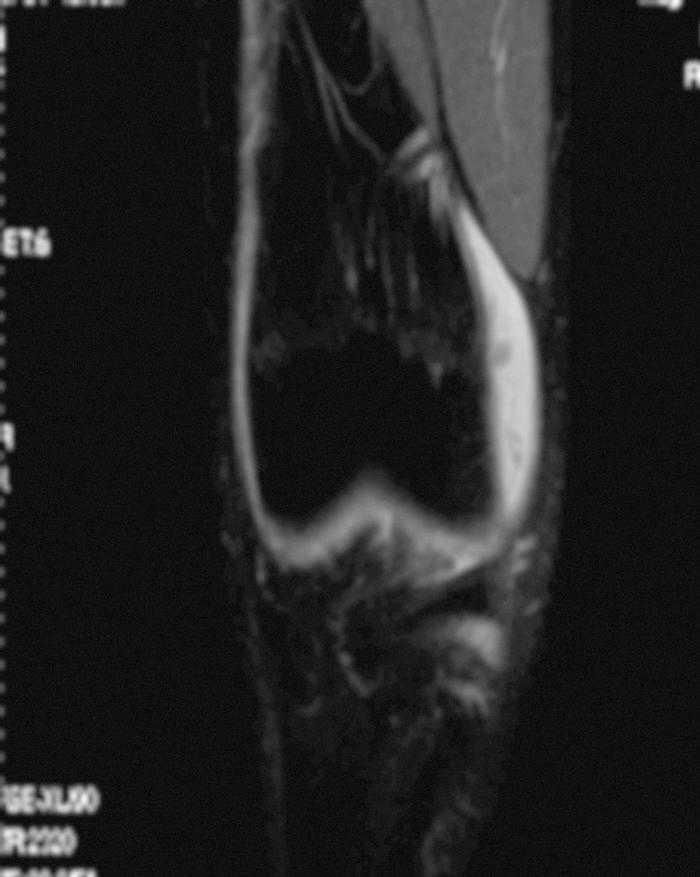

L'RM mostra (figs. 1, 3 i 5):

Figura 1 RM. Imatge potenciada en T2 amb supressió de greix. Cossos lliures en recessió articular interna.

• Múltiples cossos lliures intraarticulars.

• Vessament articular.